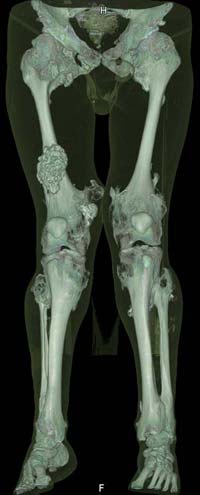

Oбратился больной 30 лет с хондродисплазией, множественными деформациями и экзостозами. Сгибательно-приводящие контрактуры Т/Б сустав, поясничный лордоз.

Интелектуально развит, работает програмистом. Болей нет. Анализы крови в пределах нормы, понижен кальций (общий Ca 1.62, N от 2.3 до 2.75; ионизорованный 0.67, N от 0.7 до 1.07) и щелочная фосфотаза -7.9. По данным КТ, оптическая плотность диафизов 150 - 200 NU (N в его возрасте 300 - 350NU) метафизарный остеопороз от 100NU до отрицательных величин - 80 NU.

Больной настоятельно просит об исправлении деформаций и удаления экзостозов области коленных суставов.

Планирую поэтапно, сначала справа, произвести вальгизирующе-антекурвационную остеотомию в подвертельной области бедра, соответственно варизирующую на голени, фиксация фрагментов спице - стержневым аппаратом Илизарова. Одновременно удалить большой экзостоз в области конен. сустава

30 years old male with chondrodysplasia and multiple exostoses admitted. Multilevel deformities, flexion-adduction limitation of hip ROM, lumbar lordosis. Intellectually developed, working in some software company. Painless. Blood tests are normal, except low Calcium (total serum Ca 1. 62, N is 2.3 - 2.75; ionized 0.67 N is 0.7 -1.07) and low alkaline phosphatase 7.9. Diaphysis bone density is about 150 - 200 NU (N in his age is 300 - 350NU). Metaphis osteoporosis is from 100NU to minus 80 NU.

Patient has strong motivation to treatment. He wants to deformities be corrected and few exostoses in knee areas be removed.

I am thinking about subtrochanteric valgization osteotomy of femur, varization osteotomy of tibia, fixation with Ilizarov - hybrid type external fixator, simultaneously removal of big exostosis in right knee area. But, before do something, I would like to know your valuable opinions. My questions are: